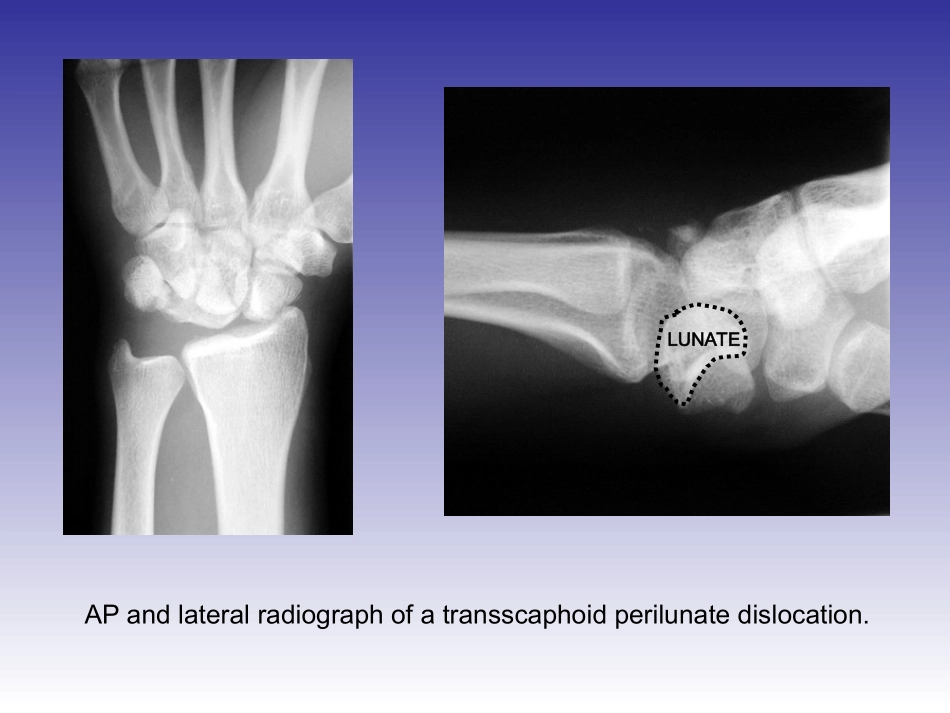

MacintoshPICTimageformatisnotsupportedLUNATEAPandlateralradiographofatransscaphoidperilunatedislocation.Thelunateisfacingdirectlyvolarandislocatedinthecarpalcanal.LUNATECAPITATEAfterattemptatclosedreductionintheemergencyroom,thepatient’slunatewasrepositionedagainstthedistalradius,howeverthemidcarpusisstilldislocatedasthecapitateremainsdorsaltothecapitatefossaofthelunate.LUNATECAPITATEThepatient’sneurologicstatuswasintact,withnormalperipheralnervesensation,including2pointdiscrimination.EPLLISTER’STUBERCLEINCISIONDorsalviewofthewristshowingtheextensorpollicuslongus(EPL)tendon.TheEPLtendonpassesulnarwardofLister’stuberclebeforeanglingtowardthethumb.Theincisionisbasedasseen(betweenthethirdandfourthdorsalcompartment).EXTENSORRETINACULUMTheincisionisbroughtdownthroughthesofttissueandtheextensorretinaculumisidentified.EPL2ndDORSALCOMPARTMENTAfterthereleaseoftheextensorretinaculumbetweenthethirdandfourthdorsalcompartments,theextensorpollicuslongusandseconddorsalcompartmenttendonsarevisualized.TheEPLandsecondcompartmentareretractedradially,whilethecommonextensortendonsareretractedlaterally,exposedthewristcapsule.LUNATECAPITATESCAPHOID(PROXIMALFRAGMENT)SCAPHOID(DISTALFRAGMENT)Afterthecapsuleisincised,thecarpalbonesarevisualized.Thelunateisvisualizedadjacenttothedistalradius.Thecapitateisseendorsallydislocatedfromthelunate.EPLSCAPHOID(PROXIMALFRAGMENT)SCAPHOID(DISTALFRAGMENT)UsingaFreerelevator,luno-capitatejointisreduced.Thecapitateisnowwithintheconfinesofthelunate.Thelunateandproximalscaphoidareintheirnormalrelationshipasthisintervalisnotinterrupted.Thescaphoidfractureisvisualizedadjacenttothecapitate.LUNATECAPITATESCAPHOIDSCAPHOIDFRACTUREAsvisualizedfromdistally,lookingdownatthearticularsurfaceofthescaphoidthatarticulateswiththecapitate,thereductionisachieved.CAPITATEAsvisualizedfromdistally,lookingdownatthearticularsurfaceofthescaphoidthatarticulateswiththecapitate,thereductionisachieved.SCAPHOID(REDUCED)CAPITATEAfterreductionofthescaphoidandradiographicconfirmation,K-wiresareplacedattheradialandulnarborderofthescaphoid,allowingacentralscrewtobepositionedbetweenthetwoK-wires.TheseK-wiresarenecessary,aswithouttwopointsofK-wirestabilizationthefragmentswillrotateononeanotherduringscrewplacementAPandlateralradiographsofthescaphoidreduction,withK-wiresandcannulatedscrewguidewire.Afterappropriatedrillingandtapping,thecannulatedscrewisplacedintothescaphoid,maintainingthereduction.Thescrewisseatedbelowthearticulatesurfaceofthescaphoid.Next,thelunotriquetralintervalisexploredandcleaned.Noticethatthescaphoidtocapitaterelationshipisnormal.Byholdingthetriquetrumawayfromthelunate,apincanbeplacedretrogradethroughthecenterofthetriquetralarticularsurfacethatwillarticulatewiththelunateonceitisreduced.SCAPHOIDTRIQUETRUMCAPITATEPROXIMALDISTALDISTALRADIUSVIEWISFROMULNARSIDEOFHANDAK-wireisdriventhroughthecenterofthearticularsurfaceofthetriquetrum.TheK-wireisthendriventhroughskinandwithdrawnsuchthatitliescompletelywithinthetriquetrum.VIEWISFROMULNARSIDEOFHANDAfterreductionofthetriquetrumtothelunateunderdirectionvision,thepreviouslyplacedK-wireisthendrivenbackacrossthelunate,holdingstability.SCAPHOIDLUNATETRIQUETRUMCAPITATEAsecondK-wireshouldbeplacedsothattherearetwofixationpointsacrossthetriquetrumtothelunate.SCAPHOIDLUNATETRIQUETRUMCAPITATETheclosureincludesthecapsuleaswellastheextensorretinaculum.Thepatientisthenplacedintoashort-armthumb-spikedcast.APandlateralradiographsdemonstratingthereductionofthetransscaphoidperilunatefracturedislocation.